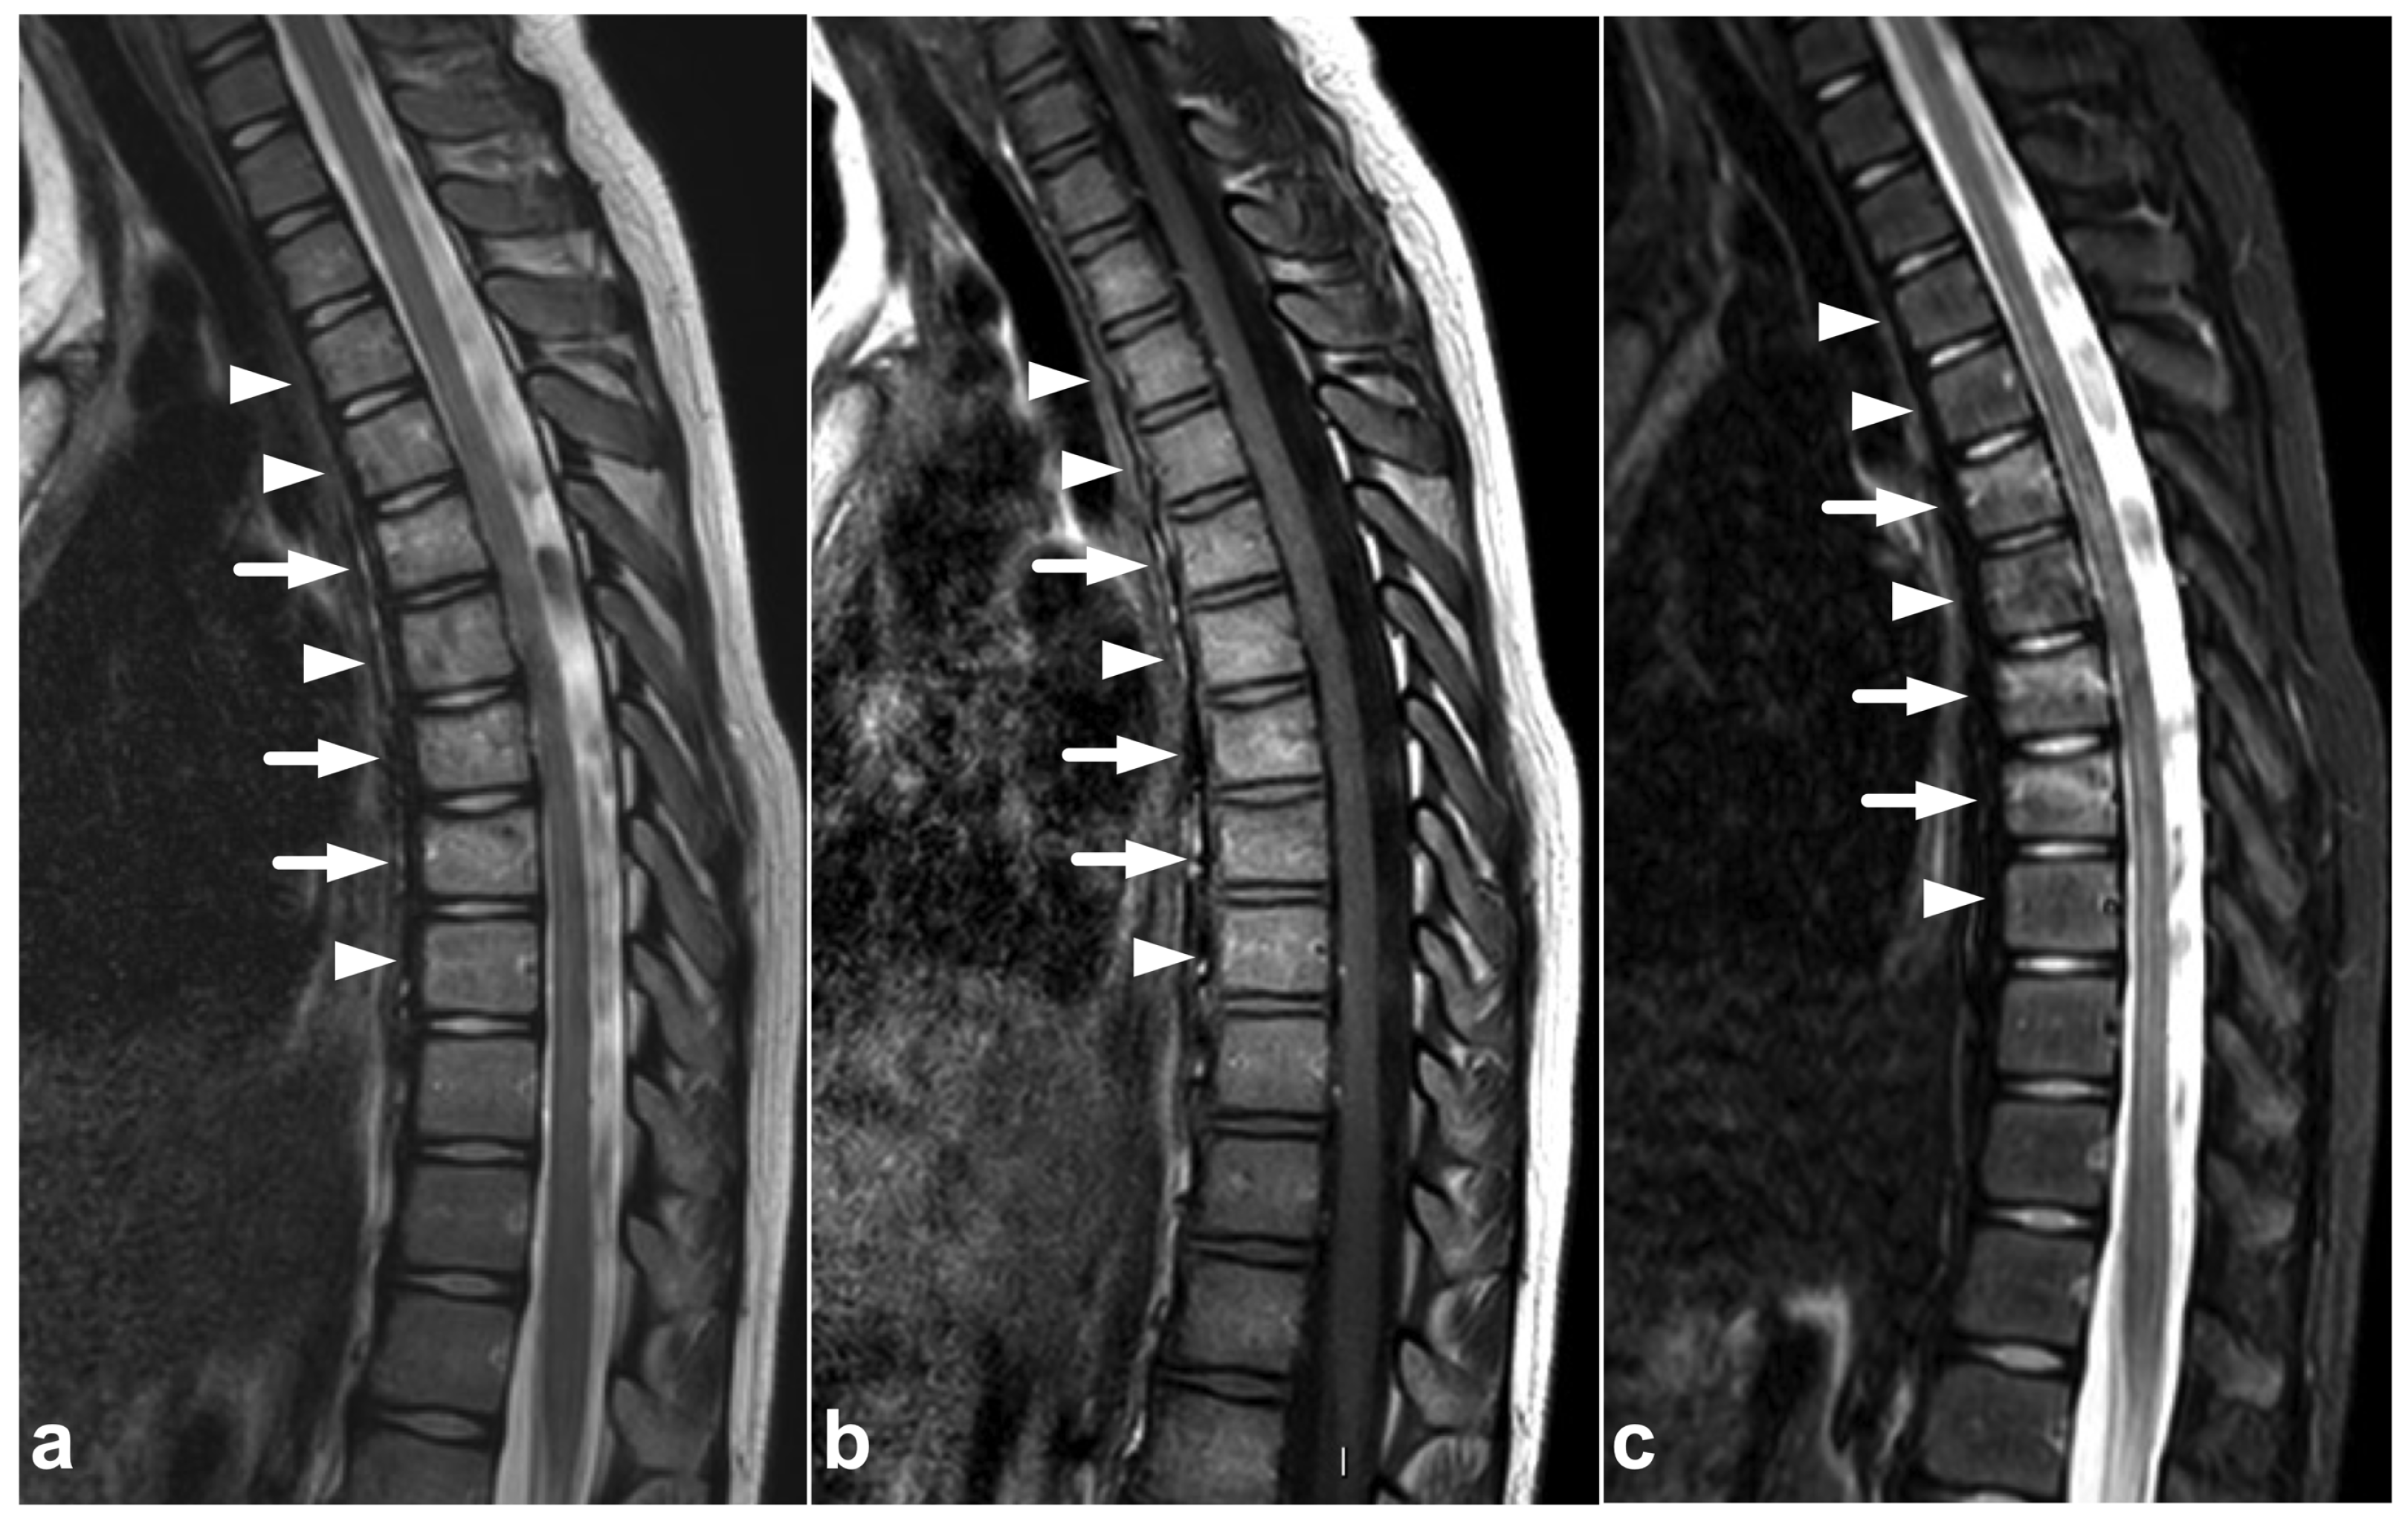

3.2. Chance Fractures